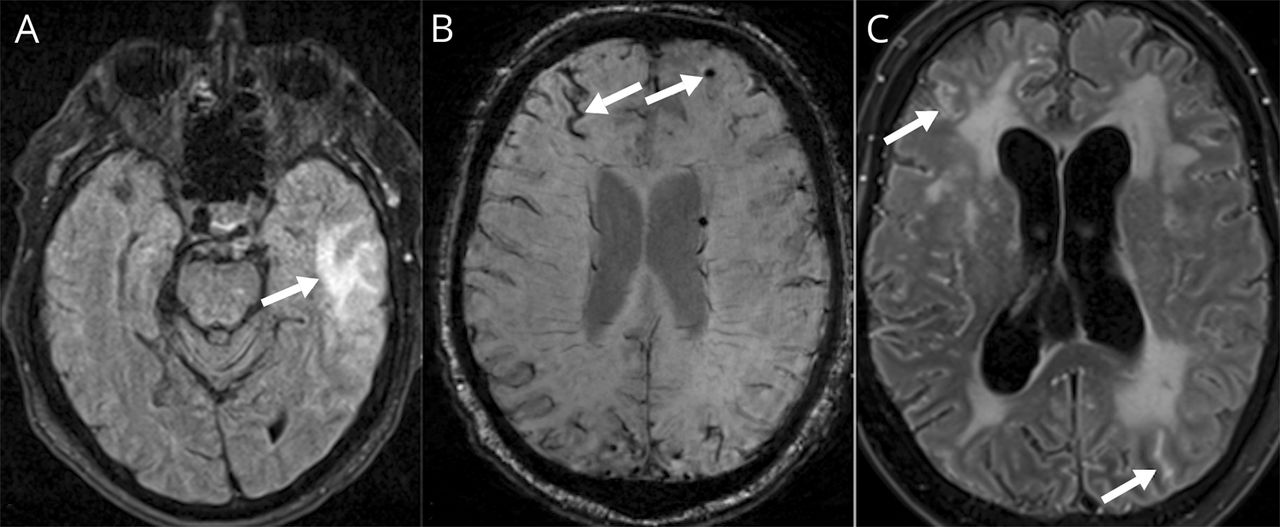

Neuropathologic检查发现明显蛛网膜增厚和4×2.5×3.5厘米亚急性左顶叶梗死。在大脑半球,显微镜β-amyloid积累被发现在皮层和arachnoidal动脉和小动脉墙壁,有时支离破碎(图2一个),局部单核炎症细胞包围。焦含铁血黄素在蛛网膜指出。除了第一个过程,蛛网膜充满了肉芽肿(图2 b)符合halo-surrounded崭露头角的有机体隐球菌sp酵母(图2 c)。附近的蛛网膜梗塞尤其相关,和动脉显示抹去动脉内膜炎,可能导致梗塞。

(A) Aβ抗体染色显示Aβ皮质小动脉内积累,偶尔与不规则干扰由于先前的淀粉样吞噬作用。(B)肉芽肿炎症蛛网膜(苏木精和伊红)。与粘蛋白(C)蛛网膜胭脂隐球菌生物物种。100µm大小栏显示。